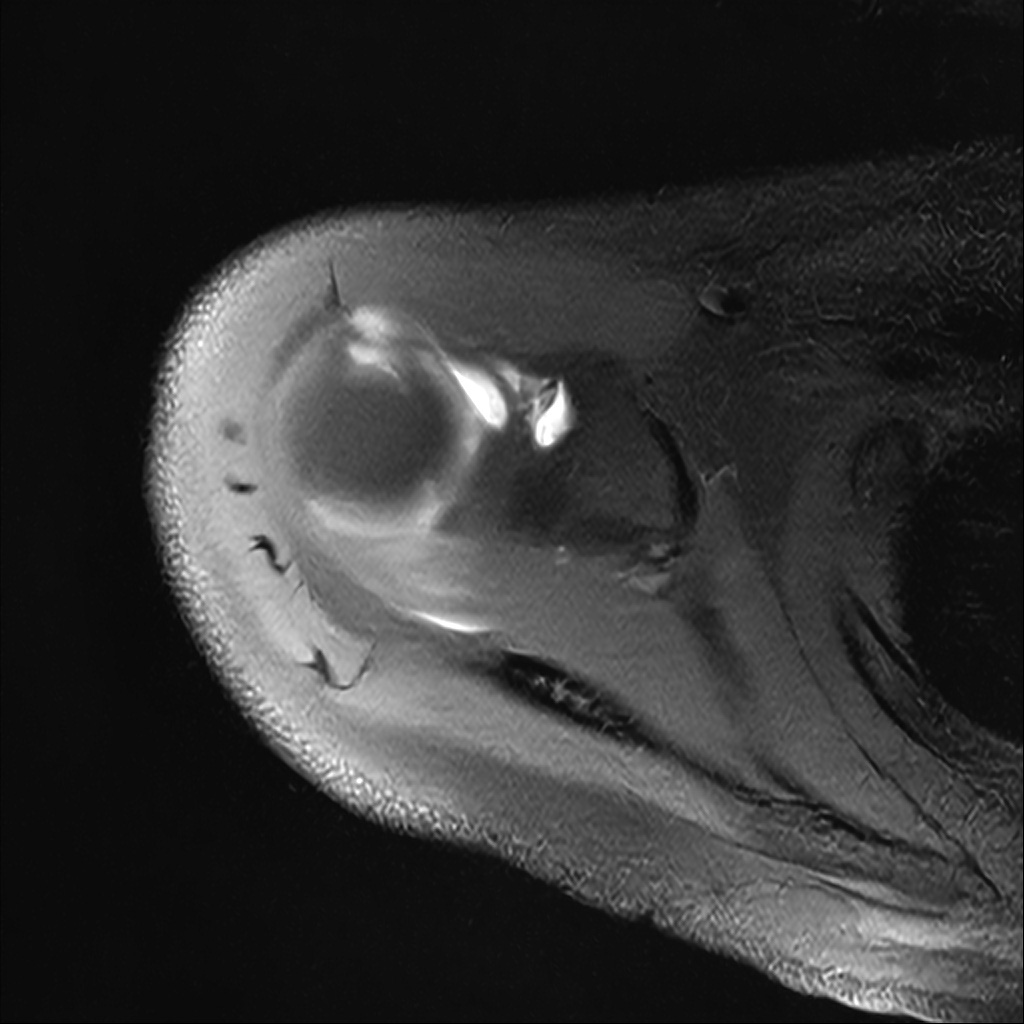

Mri 단면 영상으로 보아 어깨 관절 부위에서 이상 신호가 관찰되고 이는 관절 와순 파열의 가능성을 시사할 수 있습니다.

하지만 이영상만으로 정확한 진단은 불가능하고 정밀한 판단을 위해선 전체 시퀀스와 영상의학과 전문의의 공식판독이 필요합니다 특히 와순 파열은 위치와 동반 병변에 따라 해석이 달라집니다!